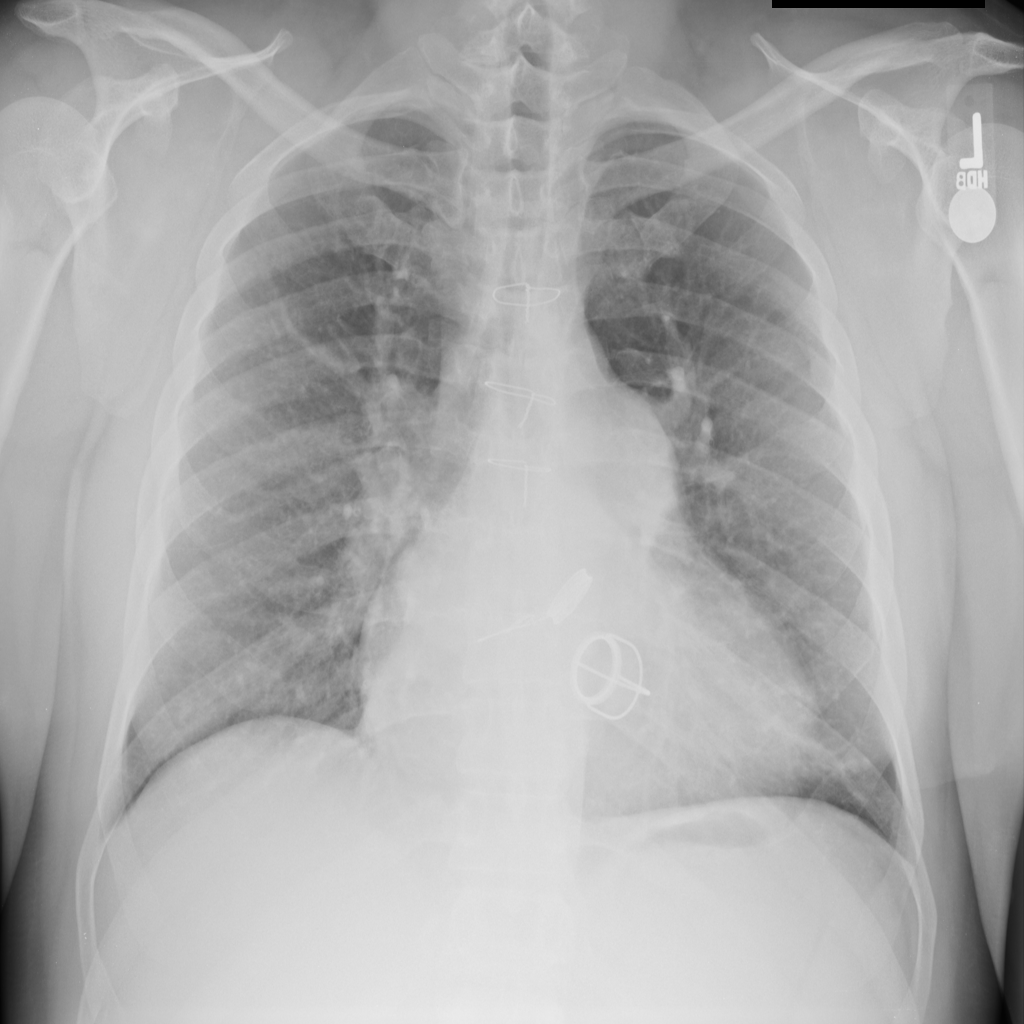

PAT-A380 · IMG-012Cardiomegaly

PAT-A380 · IMG-012

PA